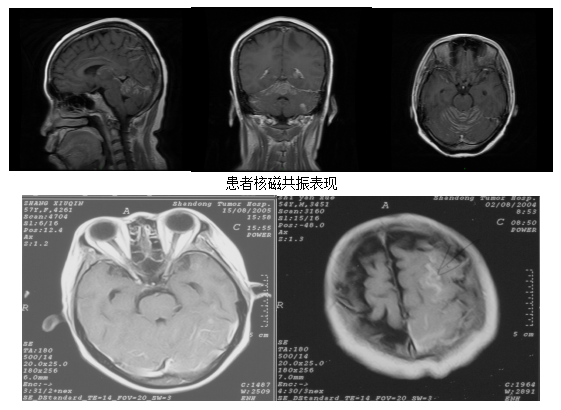

钆增强核磁共振是目前首选的脑膜转移癌影像学检查手段。对于怀疑脑膜转移癌的患者,往往需行全脑全脊髓核磁共振检查,多表现为脑/脊髓表面、脑沟、脑裂、脑池、室管膜、颅/脊神经的线样、结节样强化,常呈多灶性或弥漫性。交通性脑积水作为间接征象,也较常见。